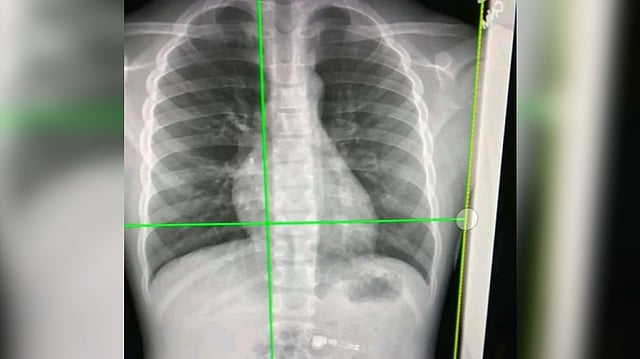

Researchers detect long-Covid’s impact via simple chest X-rays

NEW YORK: For patients dealing with lingering respiratory symptoms from the coronavirus, a simple chest X-ray can now reveal its impact on the lungs.

In a new study, researchers at the University of Iowa have developed what is called a contrastive learning model.

This model "learns" from composite 2D images constructed from 3D CT images to detect compromised lung function in long-Covid patients.

Another technique, called transfer learning, then conveys lung diagnostic information from a CT scan to a chest X-ray, thus allowing chest X-ray equipment to detect abnormalities the same as if those patients had used a CT scan.

"The new element to the model is taking information from 3D CT scans showing lung volume and transferring that information to a model that will show these same characteristics in 2D images," said Ching-Long Lin, Edward M. Mielnik and Samuel R. Harding from the Department of Mechanical Engineering in the College of Engineering at Iowa.

"Clinicians would be able to use chest X-rays to detect these outcomes. That's the bigger perspective," they said in a paper published in the journal Frontiers in Physiology.